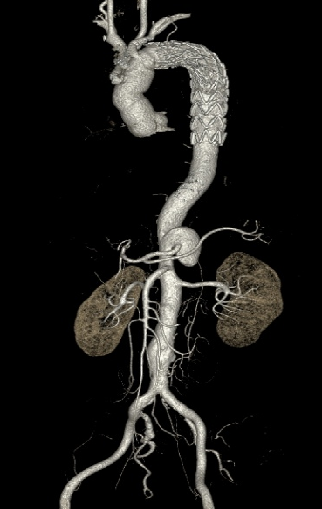

▎病例三

男,60岁,慢性夹层。2013年12月行Debranching+TEVAR术 。2016年7月复查: RTAD ,未手术。失访。

▎病例四

男, 49岁,急性夹层 。2018年11月TEVAR。一月后复查:RTAD 。 2019年1月双开窗。2019年4月2日 复查,结果良好。